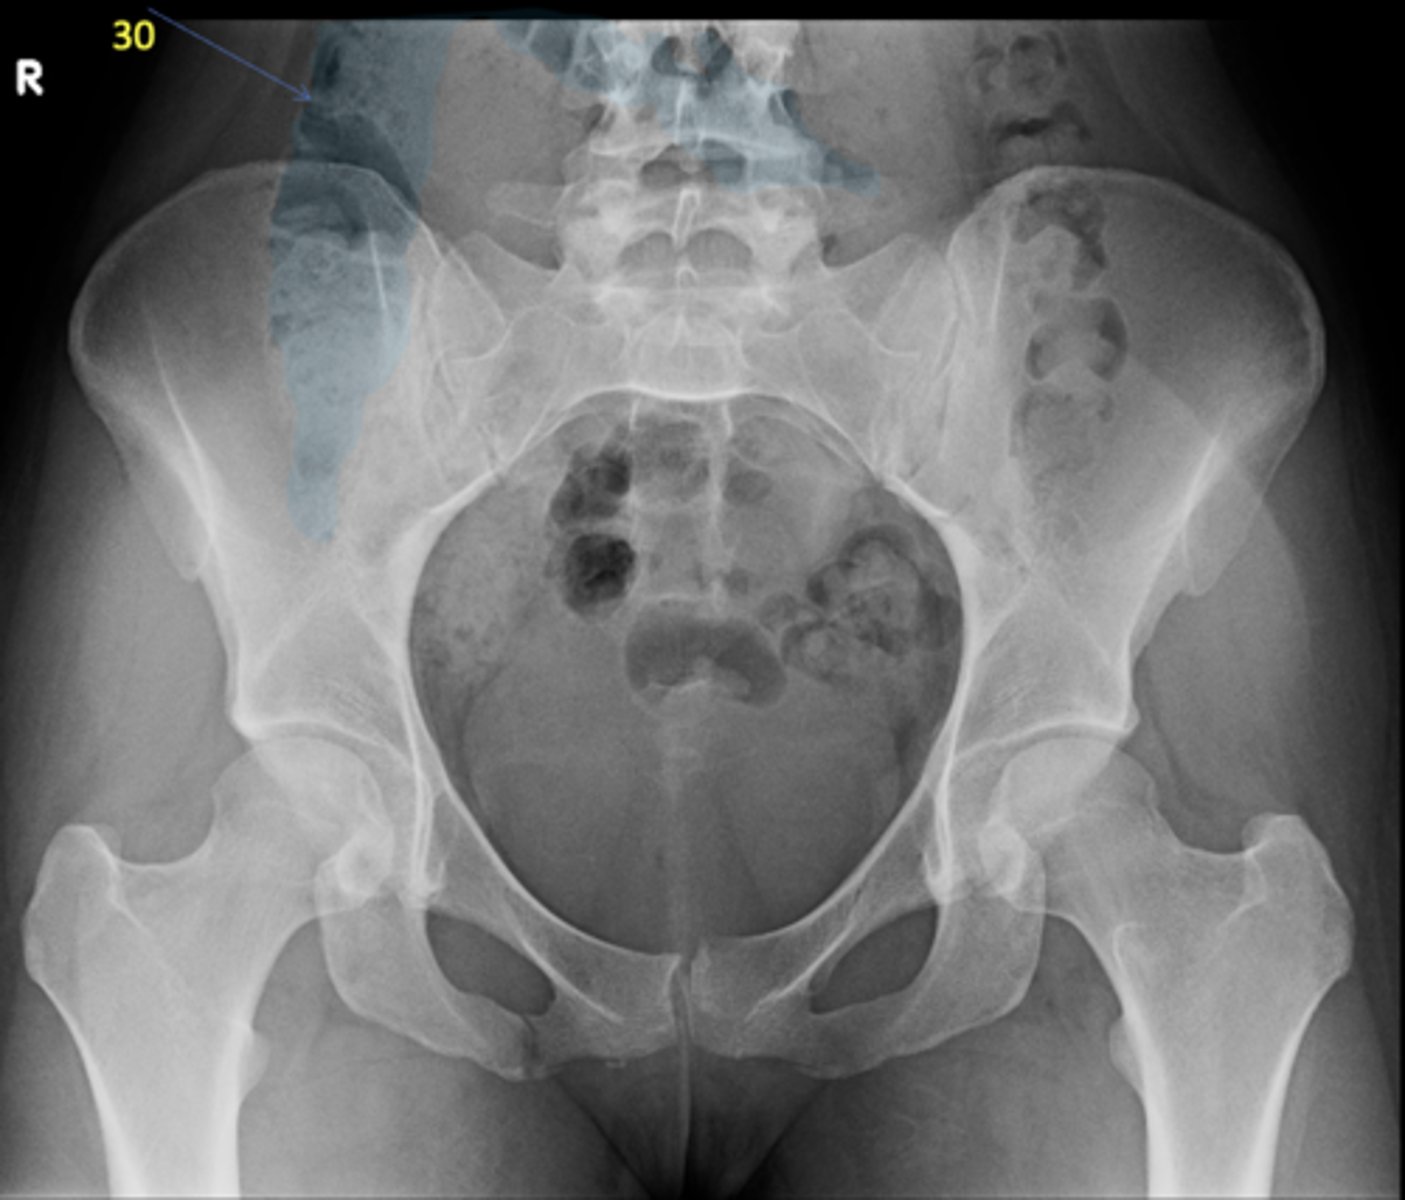

27

New cards

Ascending colon

ID 30

<p>ID 30</p>

28